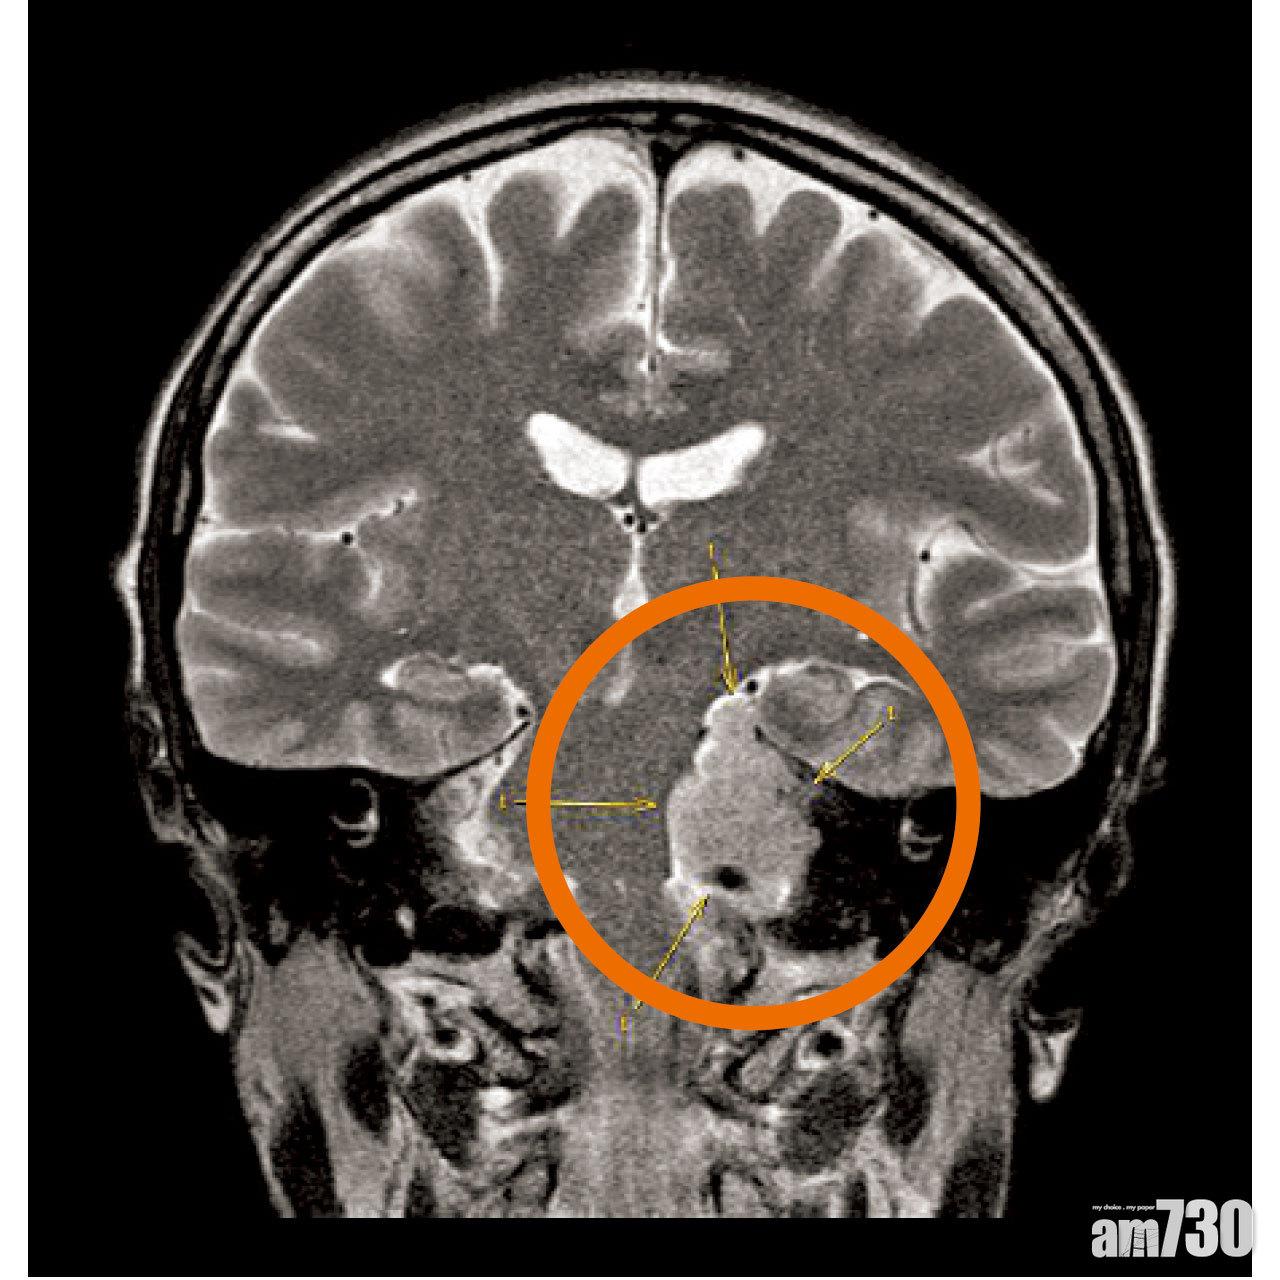

X光片顯示腫瘤的位置(紅圈示)。(陳淑莊FB)

陳淑莊昨在社交網站Facebook上載兩張腦部X光照片,顯示出腫瘤的位置及大小。她稱,於本月4日接受全身檢查,其後法庭判她罪成時,尚未有檢查報告,直至上周三接獲報告後,醫生發現其腦部磁力共振影像有異常,故委託腦專科醫生作詳細掃描,證實左腦有一個直徑4.2厘米的腫瘤。她又透露,早前已出現頭暈及面部麻痺的症狀,但當時「我自己以為身體不好,以為維他命不足」,未有意識到身體出嚴重問題,現時腫瘤已壓著腦幹致彎曲,亦壓著部分腦血管及神經,需在一至兩周內做手術切除。

腦膜瘤是常見腦腫瘤病之一,中文大學王連大腦腫瘤中心副主任陳達明解釋,原發性的腦膜瘤,85%屬良性,其餘則為惡性瘤。觀察陳淑莊發布的兩張X光片,認為腫瘤算大,位處較窄、難處理的顱底,手術風險有5%至10%,略高於一般手術。陳達明補充,「就算幾咁高手」都會安全第一,一般會先切除大部分瘤,其餘再以放射外科手術「電死」。他指術後約一周可確認是否良性瘤,一般會建議上班族休養1至2個月,若陳淑莊不幸入獄需跟進治療,監獄的醫療設備不足或需轉介治療。